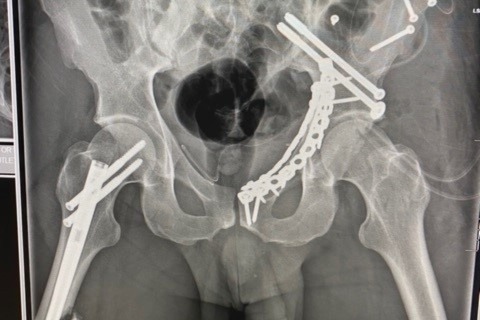

· March 19th, 2021 – Alex had an 8-hour ortho surgery to repair his femur and pelvis. I don’t know the quantity, but a rod and a gazillion screws were placed in the femur and several plates, screws and pins to repair the pelvis. The surgery was successful and we were anticipating to be discharged from the hospital in 2 – 3 days, with 2 weeks of no weight bearing on the right leg and 3 months of no weight bearing on the left leg. Alex would require a wheelchair.